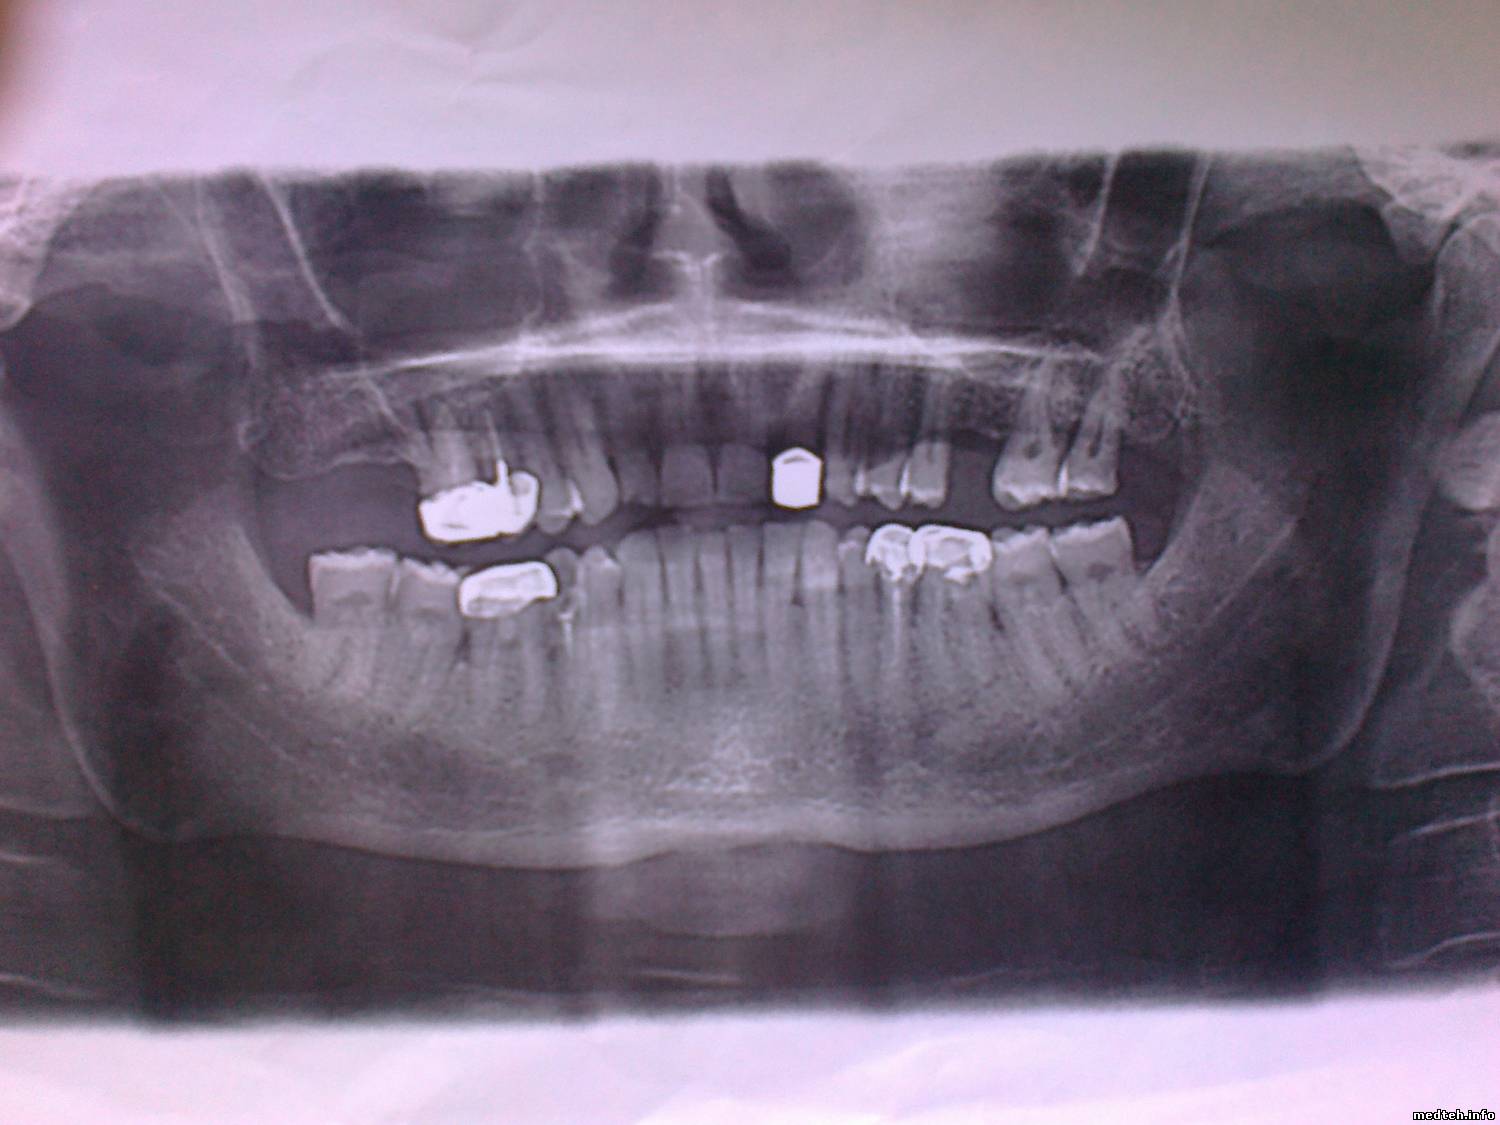

Снимок в студию !

2590983.jpg (113.9 Kb)

да уж.. как-то слабоват снимок.. режимы то какие?

Аппарат цифровой?

ошибки при позиционировании пациента: наклон головы вправо, тень от позвоночника и корни резцов не в фокусе из-за наклона головы назад. да и качество вообще какашечное.